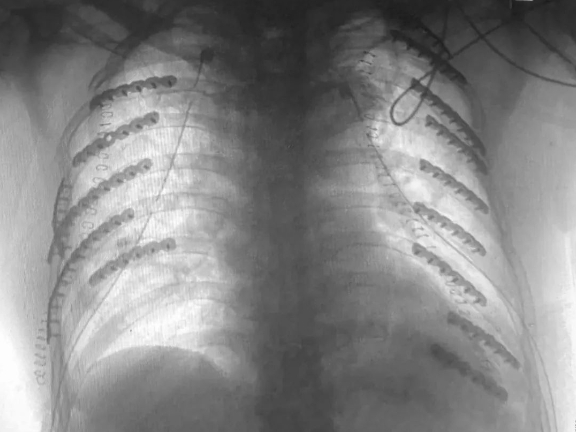

▲右侧第1-8肋骨及左侧第1-11肋骨骨折

术后,经过ICU、胸外科医护人员的细心照料,老张的呼吸循环迅速恢复。胸部CT显示,双侧血气胸消失,双肺膨胀良好,双侧塌陷的胸壁恢复正常。术后两周,老张康复,他挺起胸脯,激动地表示:“感谢积水潭医院的医护人员,是你们救了我的命!”

术后胸部CT